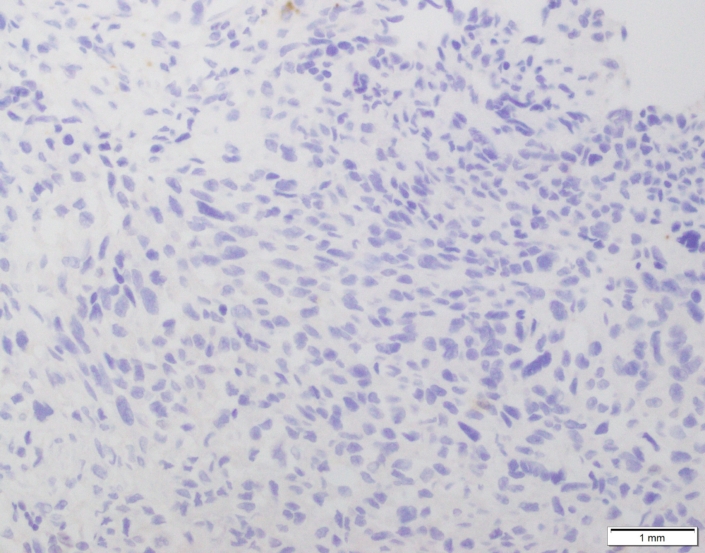

Case 03

Case presented by Dr Shaarif Bashir, FCPS (PAK), Shaukat Khanum Memorial Cancer Hospital and Reserach Centre, Pakistan